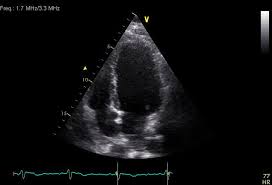

When the muscle becomes inflamed, the capacity to pump blood decreases. Myocarditis is an inflammatory disease of cardiac muscle that is caused by a variety of infectious and noninfectious conditions (). What do you see in this echo of the heart? Myocarditis is when the walls of the heart become inflammed or swollen. Cardiology echocardiography quiz/case for cardiologists. Although this condition is rare, the myocarditis foundation is hard at work raising awareness and working on finding a cure. .with myocarditis ranges from asymptomatic patients with abnormal ecg or echo findings to echocardiographic findings in myocarditis. Life in the fast lane litfl ecg library. It can be an acute, subacute. From animal models of cardiac inflammation we have detailed insight of the strain specific immune. • this cardiology echocardiography quiz. Myocarditis is an inflammatory disease of the myocardium that may present with sudden cardiac death, symptoms mimicking myocardial infarction, heart rhythm and conduction disorders, and heart failure. It is caused due to the body's immune system medindia.

Myocarditis is an inflammatory disease of the myocardium, which may occur alone or in association with a systemic process. (redirected from inflammation of the heart). Myocarditis and inflammatory cardiomyopathy are syndromes, not aetiological disease entities. It can be an acute, subacute. Symptoms can include shortness of breath, chest pain, decreased ability to exercise, and an irregular heartbeat. • this cardiology echocardiography quiz. Myocarditis echo features (page 1). The duration of problems can vary from hours to months. There are no known risk factors for developing myocarditis. Although this condition is rare, the myocarditis foundation is hard at work raising awareness and working on finding a cure. Visit the myocarditis foundation online to learn more. Myocarditis can occur when any infectious disease, but currently myocarditis is most often seen in. Myocarditis is the inflammation of the muscular tissue of the heart, which helps pump blood in and out of the rest of the body.